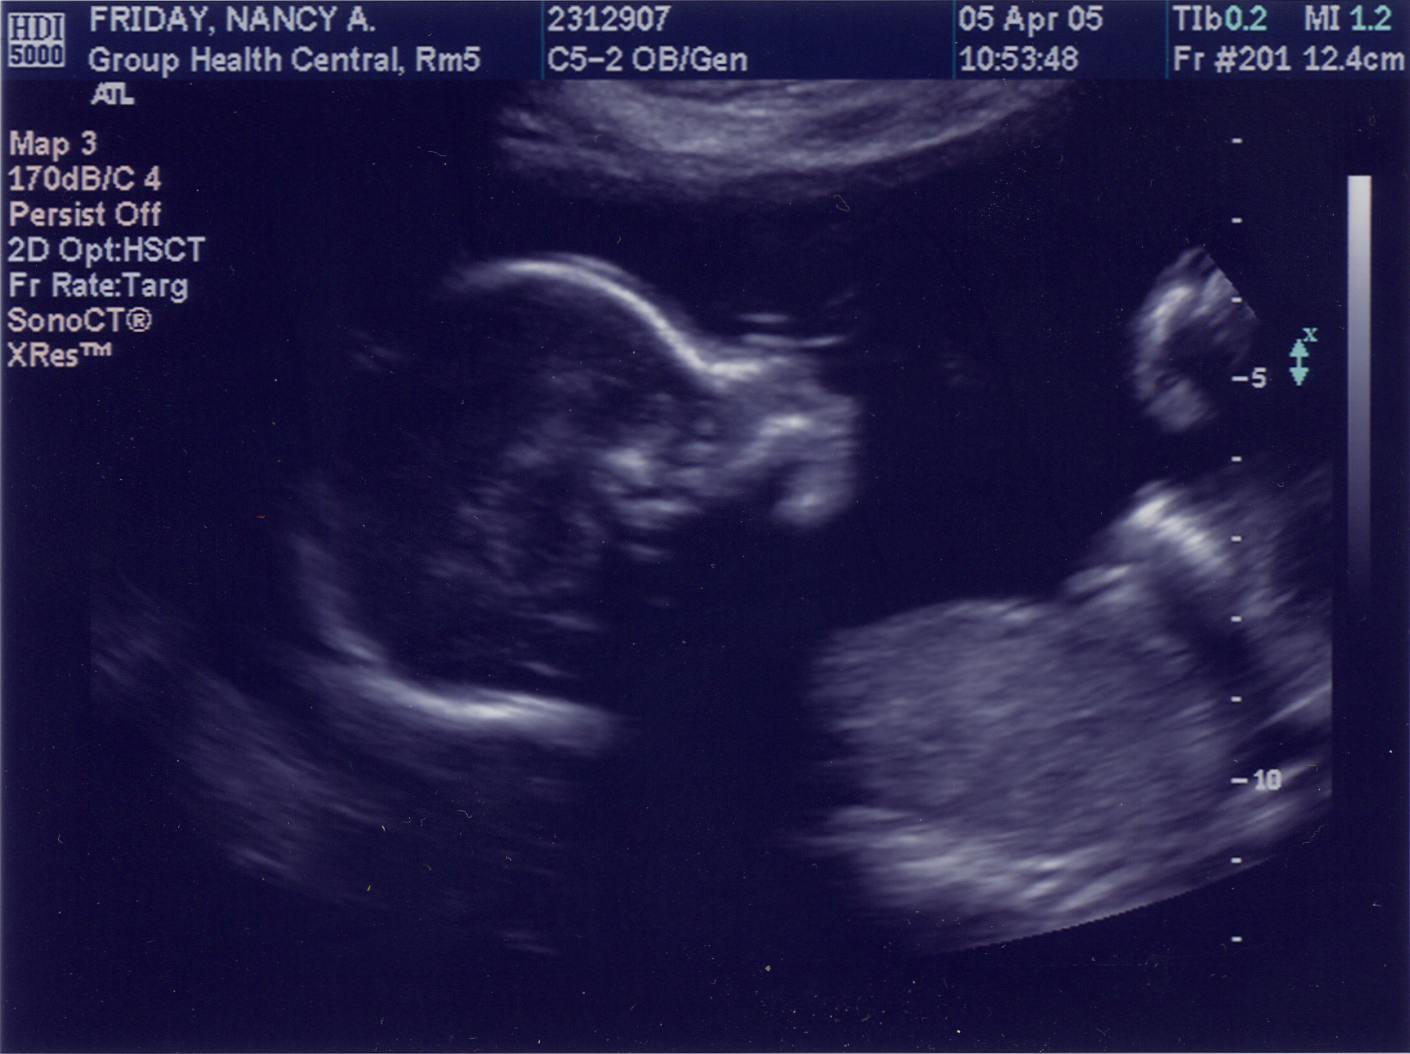

April 5, 2005 - 20.5 weeks (18.5 weeks from conception)  |